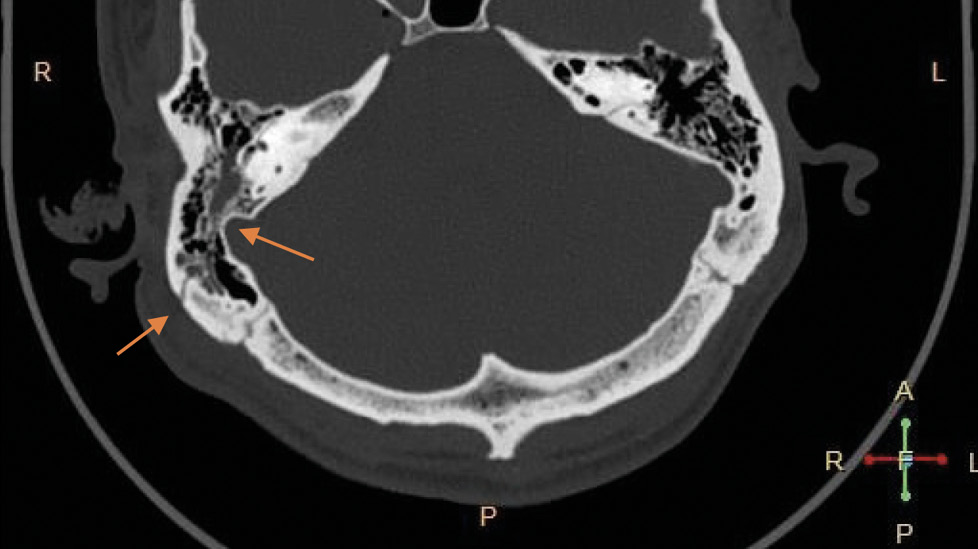

На экспертизу дополнительно представлены результаты мультиспиральной компьютерной томографии головного мозга гражданина Л., благодаря которым экспертом выявлено следующее. На серии компьютерных томограмм (с последующим 3D-моделированием) в лобно-височно-теменной области слева субдуральная гематома максимальной толщиной до 4 мм. В полюсно-базальных отделах левой височной доли определяются мелкие очаги геморрагической плотности, местами сливного характера (рис. 1, 2). Боковые желудочки симметричные. Срединные структуры мозга не смещены. Субарахноидальное пространство нивелировано слева. В бороздах мозга левой височной, левой теменной долей геморрагическое содержимое (субарахноидальное кровоизлияние), малая эпидуральная гематома правой теменно-височной области. Перелом сосцевидного отростка правой височной кости: линия перелома распространяется на пирамиду правой височной кости и заднюю стенку наружного слухового прохода (рис. 3–5). Наличие геморрагического содержимого в ячейках правого сосцевидного отростка, в антруме справа и в правой барабанной полости.

Рис. 1. Мультиспиральная компьютерная томография головного мозга: очаги ушиба головного мозга (стрелки) в полюсных отделах левой височной доли на аксиальном срезе.

Рис. 3. Мультиспиральная компьютерная томография головного мозга: перелом пирамиды правой височной кости с переходом на заднюю стенку наружного слухового прохода, кровоизлияние в ячейки сосцевидного отростка справа, в антрум и барабанную полость справа (стрелки) на аксиальном срезе.